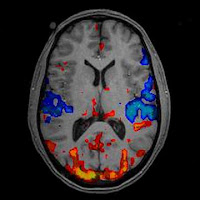

- Els homes perden el teixit cerebral durant el procés d'envelliment abans que les dones, i perden més teixits en termes absoluts. Els homes són particularment propensos a perdre teixit en els lòbuls frontals i temporals. Aquestes àrees tenen a veure amb el pensament i els sentiments. La pèrdua de teixit en elles pot causar irritabilitat i altres canvis de personalitat. Les dones tendeixen a perdre teixit en el hipocamp i les àrees parietals. Aquestes tenen a veure sobretot amb la memòria i les habilitats visoespacials, de manera que és possible que les dones tinguin més dificultats que els homes per a recordar coses i per a orientar-se a mesura que envelleixen. Els estudis de *EFC ensenyen que els homes i les dones usen el cervell de manera distinta. Quan porten a terme tasques mentals complexes, les dones tendeixen a fer ús dels dos costats del cervell mentre els homes només el costat òbviament més adequat per a això. Aquest cànon d'activitat suggereix que, en cert sentit, les dones tenen major amplitud de visió de la vida ( per exemple, consideren més aspectes del panorama general al prendre una decisió). En canvi, els homes se centren més.